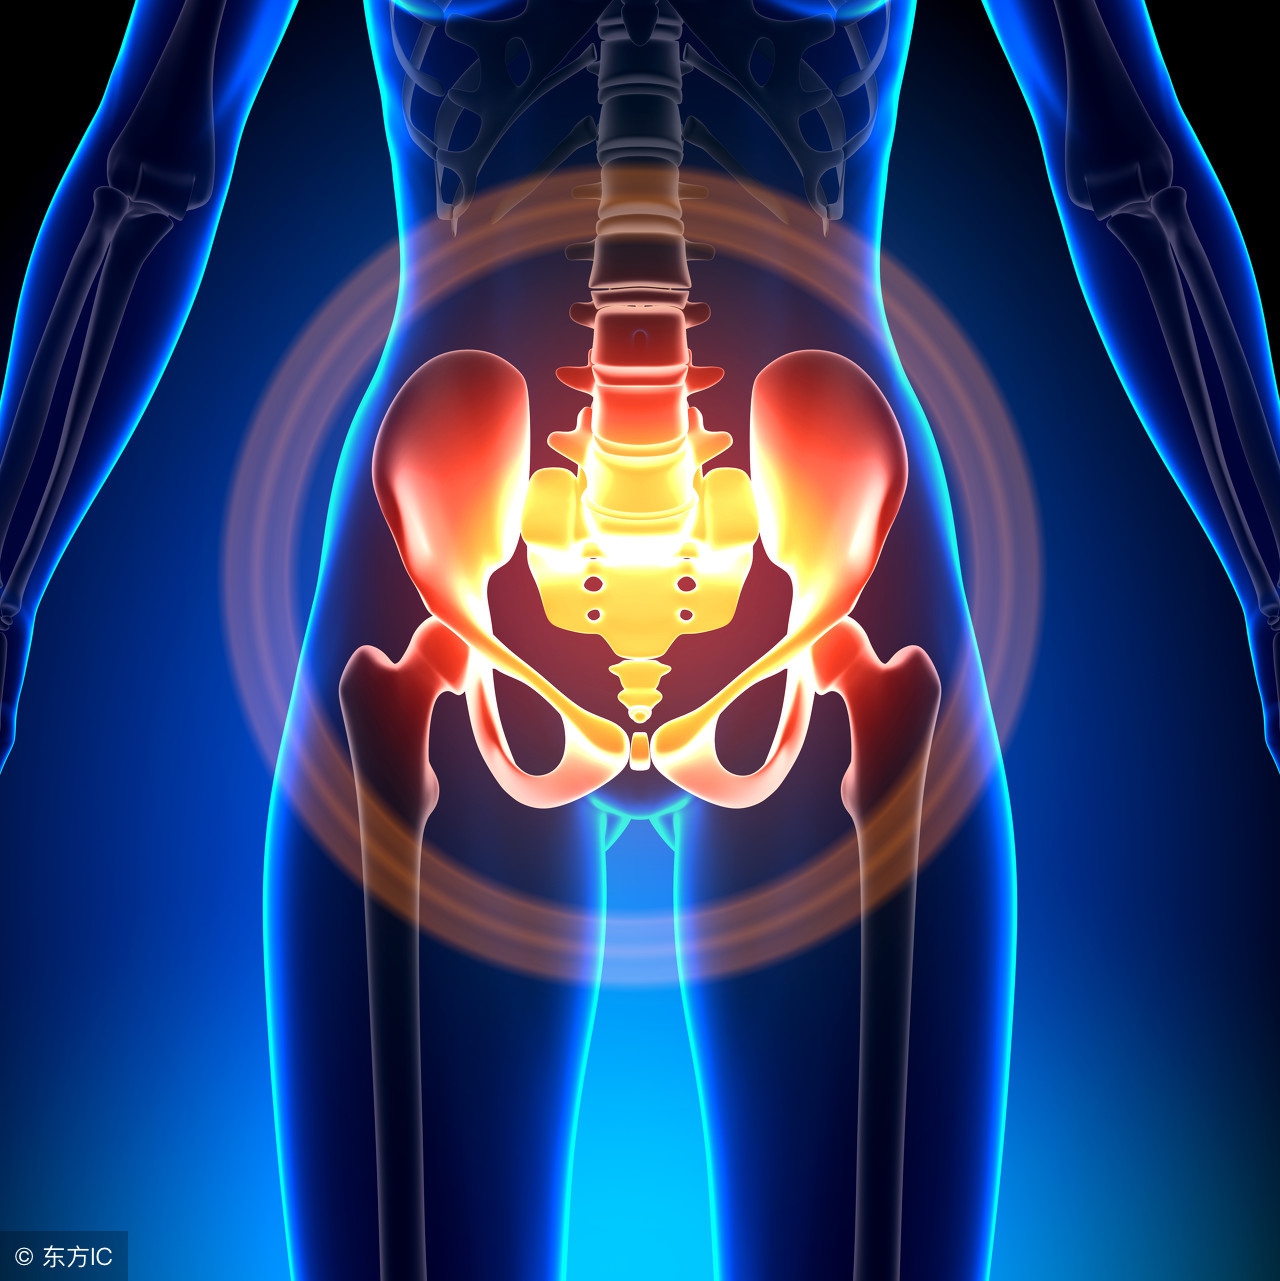

盆腔积液是一种表现而不是一种疾病,确切地说是影像学对盆腔内液体的一种描述。可分为生理性盆腔积液和病理性盆腔积液两种。

部分正常女性在月经期或排卵期会有少量的盆腔积液。这是因为在解剖上盆腔处于腹腔最低的部位,当盆腹腔脏器有少量渗出液、漏出液或破裂出血时,液体会首先聚积在盆腔,从而形成盆腔积液。如月经时,少量经血逆流至盆腔可造成盆腔积液;月经中期排卵时的卵泡液积在盆腔也可导致盆腔积液;便秘的患者,由于肠蠕动不正常,可引起少量肠液渗出导致盆腔积液。